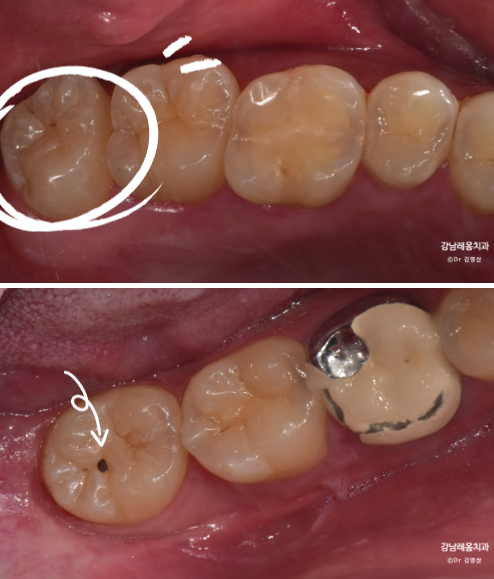

아래 케이스를 보면 위아래 사랑니가

정상 맹출되었으나 충치가 진행되어

주변치까지 영향을 주기 전에

발치를 진행하였습니다.